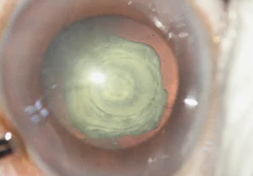

Katarak Nuklear

Katarak nuklear merupakan kekeruhan pada bagian tengah atau inti lensa. Biasanya berdiameter sekitar 3 mm, namun dapat lebih luas akibat ketidakteraturan serat lensa. Kepadatan kekeruhan lensa dapat bervariasi dan cenderung stabil, tetapi dapat pula meningkat disertai pembesaran ukuran. Katarak nuklear dapat terjadi secara bilateral maupun unilateral serta dapat bersifat diturunkan atau sporadis. Selain itu, katarak nuklear dapat disertai dengan ukuran mata yang lebih kecil dari ukuran normal dan berisiko lebih tinggi menderita glaukoma saat memasuki masa kanak-kanak.